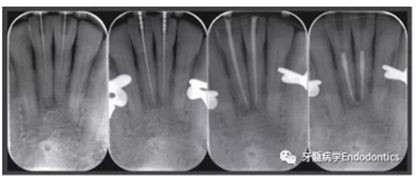

在患者下頜牙上試戴導板(帶有專門制作的金屬袖,steco-system-technik GmbH & Co. KG, Hamburg, Germany) ,判斷是否合適(圖7)。通過導板可以定位根管入路點,并微創(chuàng)去除牙釉質,直到牙本質暴露。鉆針轉速設定為10000RPM,上下提拉鉆頭獲得根管根尖1/3的入路(圖8)。當鉆針柄接觸導板上的金屬袖時,鉆針尖端到達目標位點。整個根尖入路的制備過程耗時約10分鐘。圖9展示了微創(chuàng)預備的根管入路。然后進行常規(guī)的根管治療。用1%的次氯酸鈉沖洗根管,單支往返銼(R25, VDW, Munich, Germany)預備根管,超聲蕩洗,干燥根管后用氫氧化鈣(Ultracal XS, Ultradent Products Inc, South Jordan, UT, USA) 封藥,暫封(CavitTM, 3 M ESPE) 。兩周后,患牙均無叩痛,使用熱牙膠垂直加壓技術和環(huán)氧樹脂糊劑(AH Plus, De Trey, Konstanz, Germany)充填根管。圖10為根管治療過程中拍攝的x線片。髓腔清理后,使用復合樹脂(Filtek Supreme XTE, 3 M ESPE, Seefeld,Germany) 和多步法粘接劑(Optibond FL, Kerr, Orange, CA, USA).充填。

圖10.根管治療過程中拍攝的X線片。(a)微創(chuàng)根管入路制備完成拍攝的定位片,(b)根管長度測量,(c)試主尖片,(d)去除冠方根充填物后的最終根充效果。